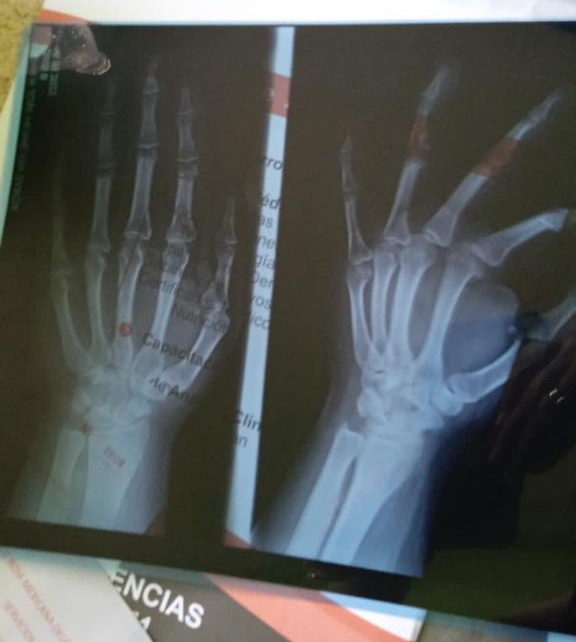

Las agresiones contra Mario*, el joven de 15 años, han venido subiendo de tono, detalló en entrevista. Debido a que la madre del joven es lesbiana, consideró que la violencia radica en la lesbofobia que los adolescentes manifiestan en su agresión. Y esta ha escalado niveles, pues a Mario* le fracturaron la mano derecha y le provocaron diversas lesiones que fueron atendidas en el servicio médico de la Cruz Roja durante la madrugada del lunes 16 de mayo de 2022.